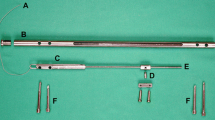

This novel callus distraction system (CDS) was designed for segmental bone transport in the femur but can be applied to the tibia and humerus also [23]. Distraction osteogenesis is achieved by using a fully implantable system comprising a tube-in-tube system and a wire traction mechanism (Fig. 1). There are three different components enabling a maximum distraction distance of 216 mm for the femoral version of the nail:

The CDS nail

The femoral version of the CDS is a 340- to 420-mm straight nail. It has an external diameter of 13 mm with additional 1-mm longitudinal wall-strengthening bulges leading to a maximum diameter of 14 mm. With an internal diameter of 10.2 mm, the wall thickness measures 1.4 mm (1.9 mm with bulge). To allow transport of a bone segment without rotational deformity, the nail is supported by two proximal and two distal transverse interlocking holes with a diameter of 6 mm each. In addition, there is a 6-mm slit over a length of 216 mm within the nail (Fig. 2).

Mechanism

With an external diameter of 10.15 mm, the cylinder-shaped mechanical system of the CDS is fully inserted into the nail (Fig. 3). The in-line mechanics consists of a threaded rod and a threaded rod spindle on top. The connection between the bone segment and the threaded rod is produced by a spindle nut attached to the threaded rod (Figs. 4, 5). A traction wire connected to the mechanics creates a force via functional change in the length of the traction wire, occurring on active or passive movement of the knee joint. Movement of the traction wire and tensile force are converted inside the mechanism, which acts in a similar way to a mechanically driven gyroscope, into a rotational movement of the threaded rod which then transports the spindle nut and correspondingly the bone segment connected to the spindle nut. Thus, the mechanism, once set in motion inside the nail’s lumen, turns the threaded rod by converting the translational movement of the traction wire.

Traction wire

A traction wire is connected to the mechanism on the one end and fixed to the tibial tubercle on the other using a screw as an anchor (Figs. 1, 6). The wire is moved by flexing the knee joint generating a traction force which then triggers the mechanism for bone segment transport. The length of the wire is adjusted at, for example, 90° flexion of the knee joint. Further flexion of the knee joint leads to force transmission as tension is put on the pulling wire (Fig. 7). Knee flexion of more than 120° generates a traction force high enough to trigger the mechanism. The system can be regarded as an all-or-none principle. Flexion of the knee joint from 90° to 119° generates an increasing traction force on the wire, but further traction force is required to release the irreversible bone segment transport. Each flexion of the knee joint over 120° results in a bone segment transport distance of 0.25 mm. It should be noted that the angle that triggers the mechanism is adjustable according to the patient’s range of motion. The designated distance of bone segment transport is 1 mm per day.